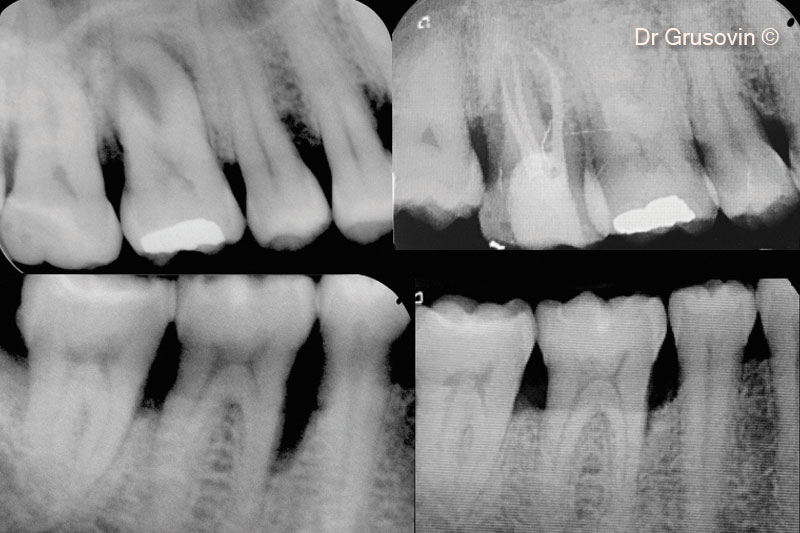

3. X-ray #16

10. X-rays #46